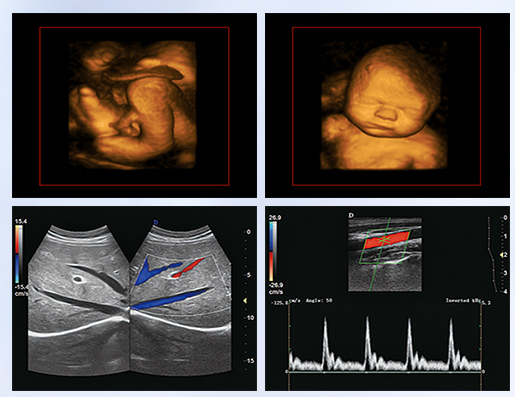

超聲學科的發展史,猶如一卷悠遠綿長的畫冊。從黑白B超機到彩超機,從一維、二維向三維立體動態,從推車式B超機到便攜式彩超機,從觀察人體解剖學到分析人體組織內細微結構和功能。隨著科學技術的不斷發展,B超機功能也越來越方便強大。

超聲作為一門醫、理、工相結合的學科,涵蓋超聲診斷、超聲治療和超聲工程技術等門類,其在臨床診斷和治療中發揮著日益重要的作用。B超機借助各種超聲探頭,以精湛的技術和嚴謹的態度掃描著人體臟器內的細微病變,給臨床提供準確而快捷的檢查報告,在影影綽綽間,發現病魔的蛛絲馬跡中,用“金睛火眼”挽救患者性命……超聲的每一幅圖像,都是靠超聲醫生親自探查并采集的,每一個患者,至少都有10張以上的圖像存儲,對于比較復雜的病例,有幾十甚至上百張。而且所有的圖像,都需要超聲醫生在邊探查的時候,邊思考分析。這,是一個真正手腦并用的工作。